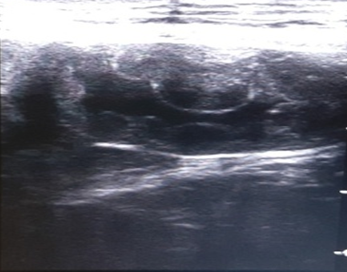

Canine pyometra is one of the most frequent reproductive organ disorders in reported in intact female dogs, particularly during the diestrus phase of estrus cycle and progesterone dominant uterus.1 Pyometra is accumulation of exudates within the uterine lumen, typically occurring during or immediately after a period of progesterone dominance. Clinical signs associated with this kind of disorder include lethargy, anorexia, polydipsia, polyuria, vomiting and unusual vaginal discharge (Kuplulu et al., 2009).2 The most accurate method of diagnosing pyometra in canines is ultrasonography.3 Both qualitative and quantitative examination is possible in diagnosing pyometra.4 In case of Pyometra, uterus will appear as distended and anechoic sacs are visualized due to pus accumulation. The advantage of ultrasonography is that it can detect the intrauterine fluid even in smaller quantity and also detect the abnormal changes in the ovaries and uterine tissue.5 Depending on the extent of uterine involvement, ultrasonographic features of pyometra may vary, the areas of uterine involvement may appear as hypoechoic or anechoic areas like if moderate involvement is there, it will appear as hypoechoic, roughly round structure ventral to ventro-lateral to the anechoic urinary bladder in transverse section. On ultrasound examination, cystic endometrial hyperplasia (CEH), which precedes pyometra, appear as small, cyst like fluid-filled regions within the endometrium (Figure 1). Similarly, transabdominal ultrasonography is effective way in diagnosing closed type of pyometra. A characteristic multiple anechoic sacculations with changes in the uterine wall thickness is visible as depicted in Figures 2–4. Therefore, ultrasound can be used as non-invasive and rapid diagnostic technique to detect the uterine pathologies like CEH and pyometra.6–10

Figure 4 Ultrasonographic view of uterus showing corrugations of uterine wall suggestive of CEH and anechoic to hypoechoic contents in the lumen.